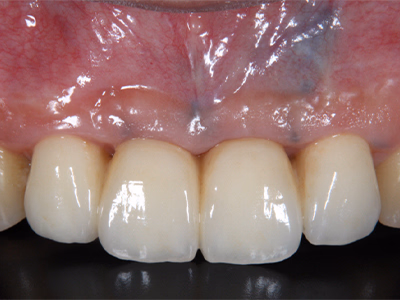

治療後

奥歯がしみて痛む(右上第2大臼歯 #27)

治療内容

- ① CT診査で根管形態を把握

- ② マイクロスコープ+ラバーダム下で抜髄(根管清掃)

- ③ 2回目で根管充填・ファイバーコア封鎖

- ④ 3回目:支台歯形成・印象

- ⑤ 4回目:セラミッククラウン装着

約1ヶ月半(1回の治療:1~2時間×4回)

- マイクロエンド 132,000円

- ファイバーコア 22,000円

- 仮歯 6,600円

- セラミック冠 165,000円

- 術後の腫れ・痛み・出血

- 根管内組織を完全に除去できない場合、慢性根尖性歯周炎へ移行する可能性

- 定期的なチェックが必要

抜髄後数日で痛みが消失。

セラミック装着後も正常に咀嚼でき、現在は年1回の定期検診で良好な経過を維持。